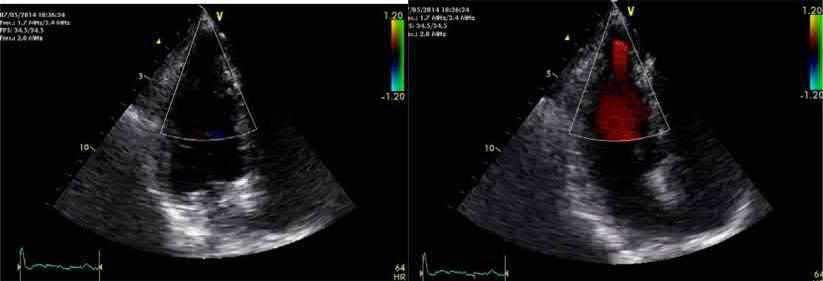

A 60‐year old woman with epigastric discomfort. Her medical history included a treadmill exercise test several years earlier because of negative T waves in V2 to V4 found on a routine

ECG (Figure). The ECG findings were considered a normal variant in a woman and the treadmill test was negative. The ECG shows sinus rhythm with mild biphasic T waves in V2 to V4.

An echocardiogram was performed (left diastole, right systole)

Correct answer: 1

The echocardiogram (of intermediate quality) detected an apical aneurysm. The ventricular aneurysm with a paradoxical expansion during systole and end‐systolic flow pattern from the ventricle to the aneurysm was better demonstrated with CMR (next figure, arrows) (Fiol M, et al. Int J Cardiovasc Imaging. 2015;31: 1261–1262). A “normal variant” is uncommon, but still possible, at the age of 60.

A 68‐year‐old diabetic patient presented with precordial pain radiating to the back. The ECG (Figure) was interpreted as non‐diagnostic.

An aortic CT was performed to rule out aortic dissection.